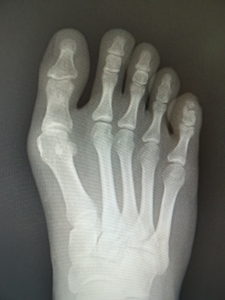

おおむね、外反角が30度以上になると、保存治療はもはやあまり有効ではありません。症状が強く、患者さんと良く吟味の上、希望されれば手術へと進みます。他に根治療法はないが、手術なら根治できます(図5)。ただMP関節の変性性変化があると、痛みや拘縮が残ることがあります。

(図5)

手術前 手術後4年

(図6)

手術前 手術後

(図7)

この手術は、人工関節手術などと異なり、何も人工物を体内に残さない、優秀な手術です。罹患以前の状態に戻るという意味で、本来的な根治術といえるでしょう。変形が治るので、靴が履きやすくなり、しっかりリハビリしてMP関節の動きがよくなれば、運動も自由に行えるようになります。